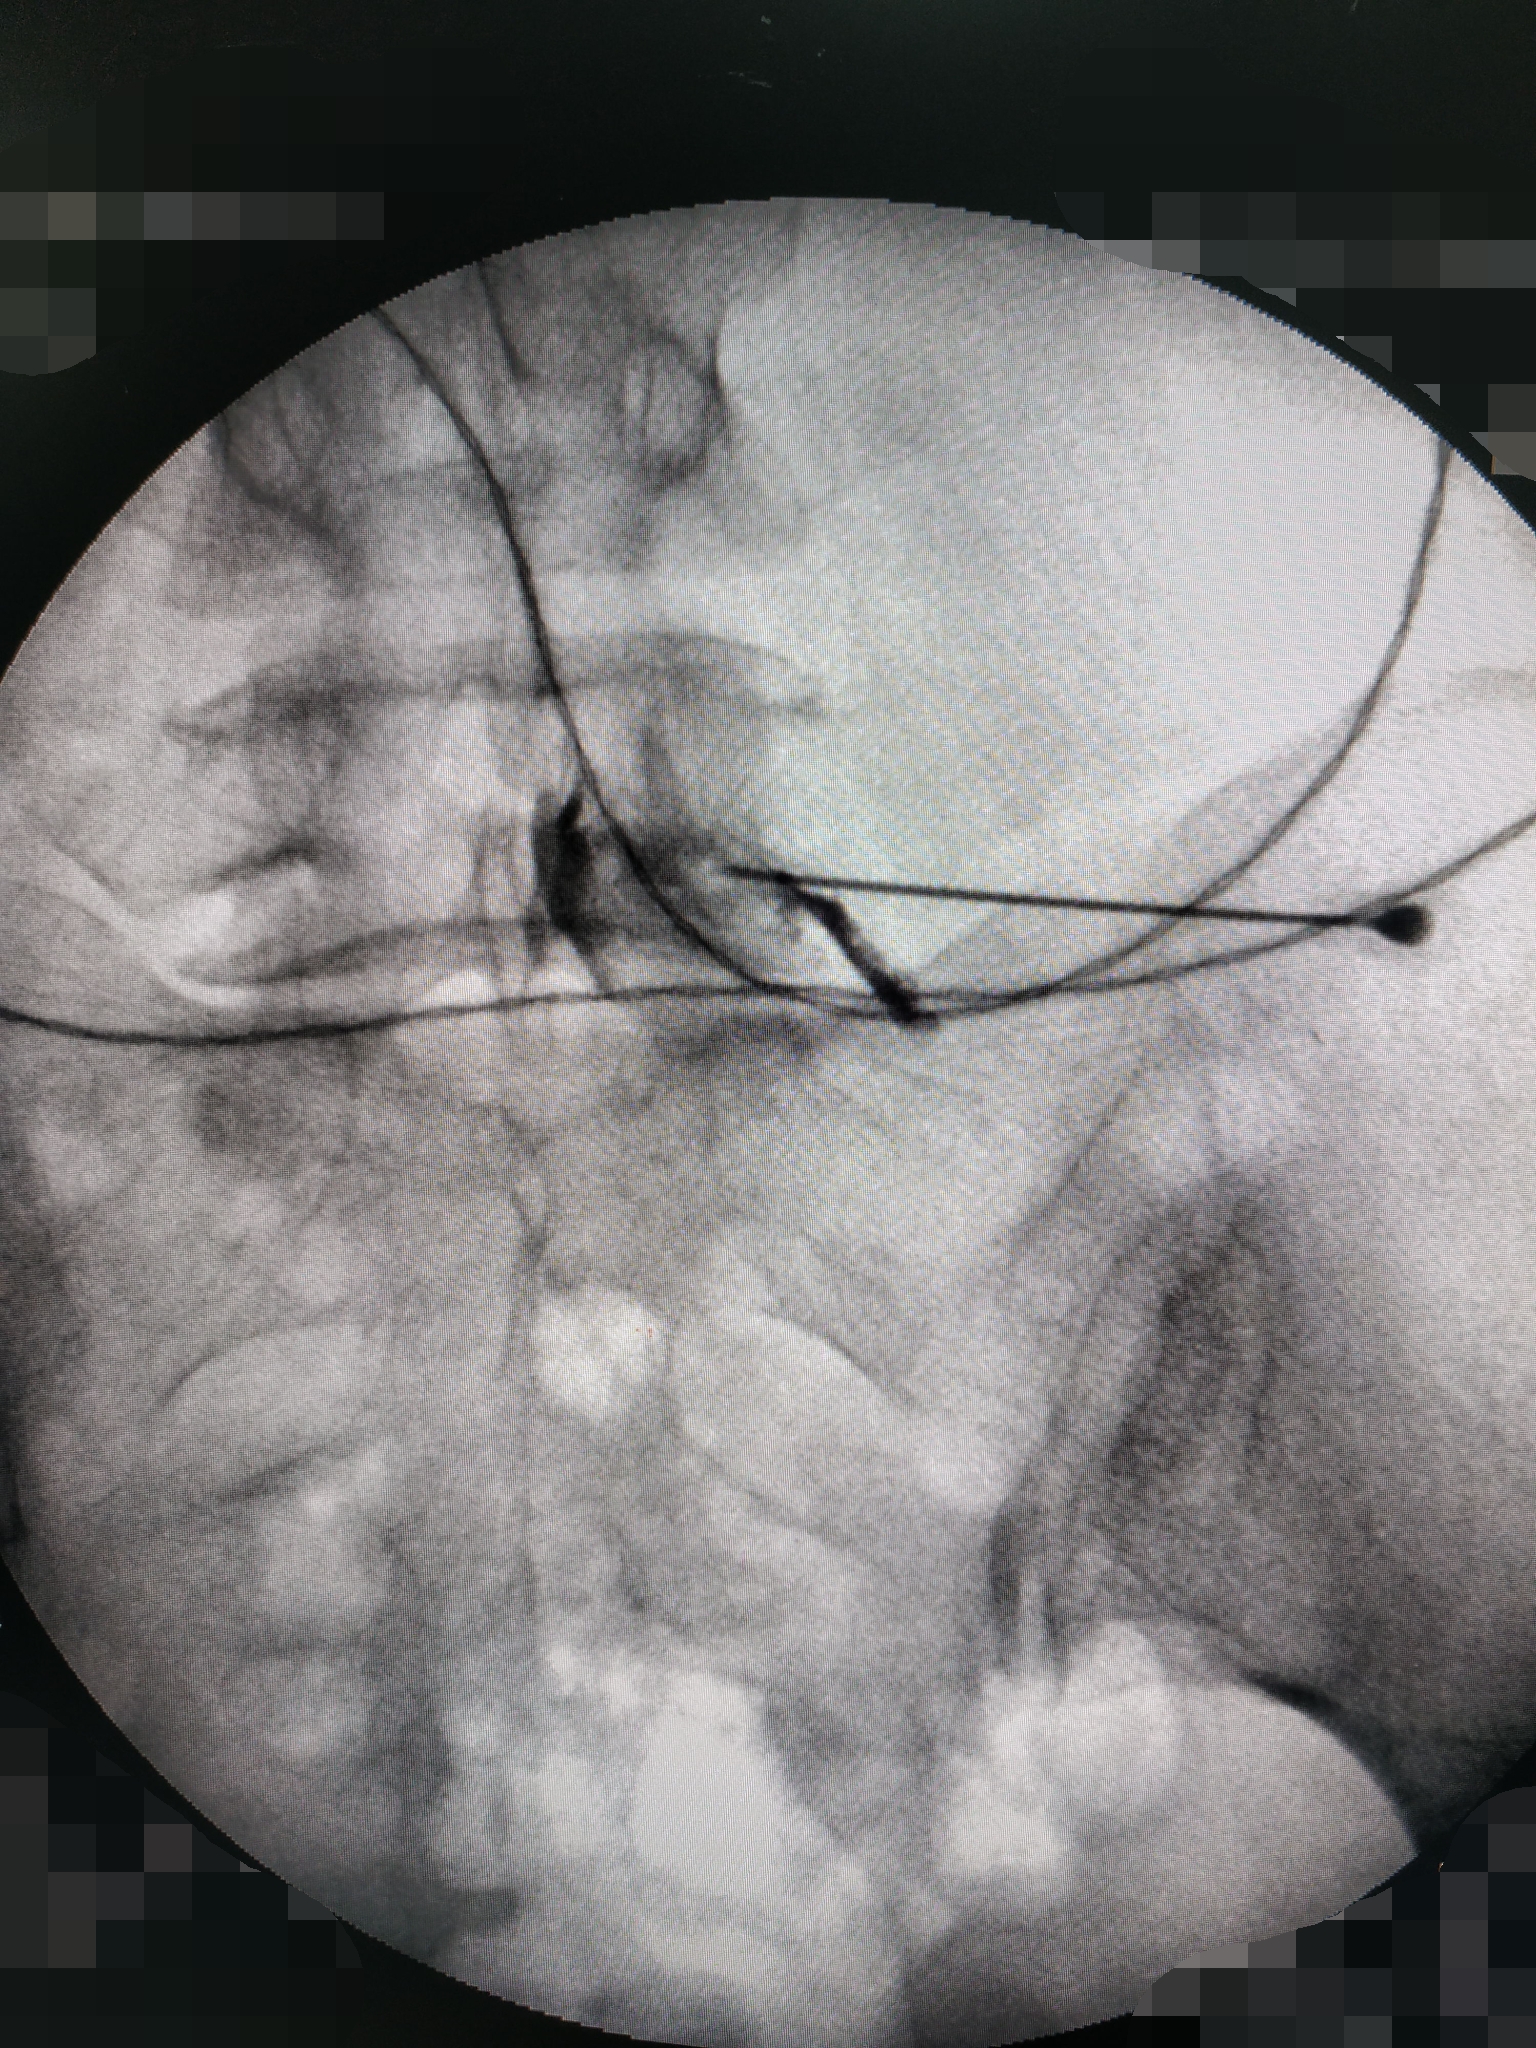

针灸康复科副主任肖祖伟和科室骨干李有超正在DSA下进行射频脉冲治疗

在DSA下进行操作治疗